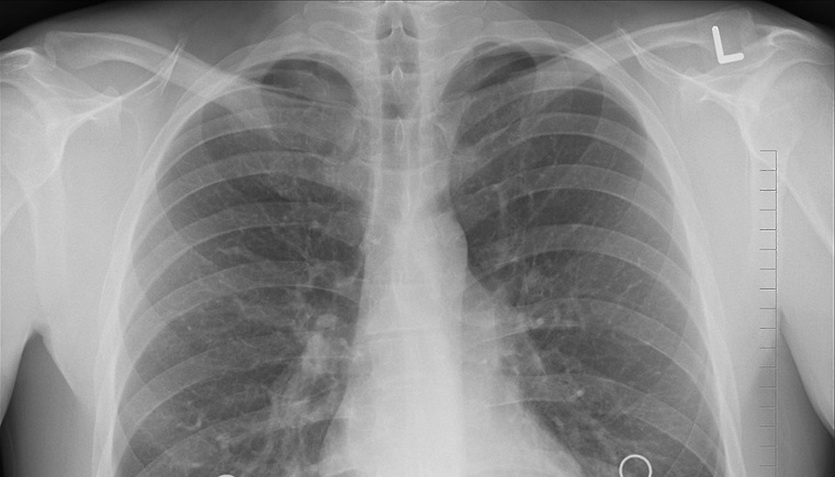

Пресловутый COVID во многих случаях первично диагностируется уже на обычных рентгеновских снимках. То же с другими проблемами легких.

Даже на рентгеновских плоских снимках видно COVID